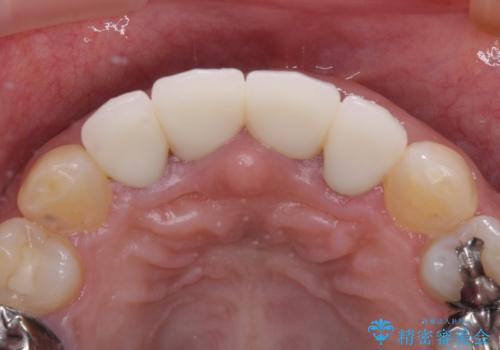

不適な仮歯の影響で歯肉が腫れていたため、新しい仮歯に替えた後に歯肉の腫れが引くのを待ち、オールセラミッククラウンにて補綴することとしました。

根尖病変が原因で、膿が出てきている歯があったため、仮歯を置き換える際に根管治療を行うこととしました。

仮歯を変えたことで歯肉の腫れは引き、根管治療も功を奏して膿の出口はきれいに消退しました。